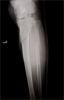

Post

Op

Xrays : alignment maintained with restoration of joint height